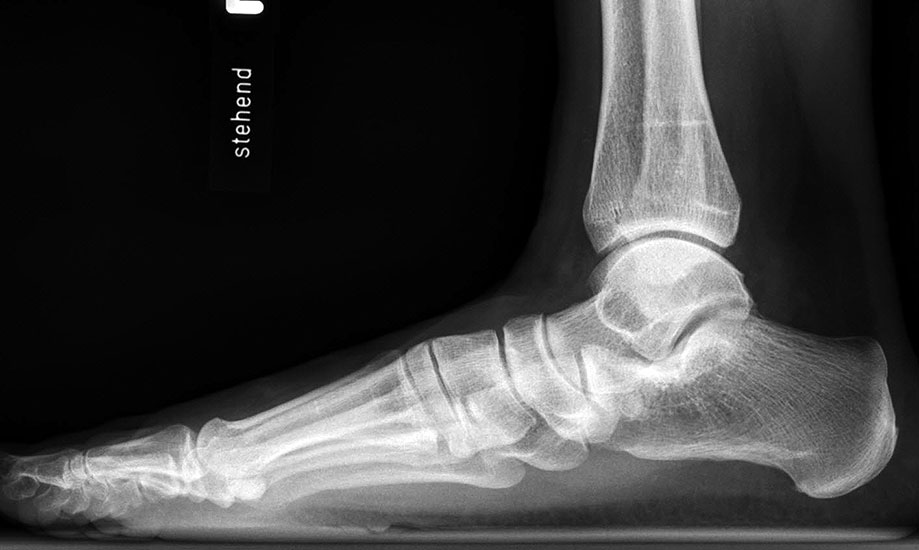

Konventionelles Röntgen

Stehende Aufnahmen des Fußes dorsoplantar (dp) und seitlich sowie des OSG anteroposterior (ap) sind die Grundlage der konventionellen Röntgendiagnostik (Abb. 5). Ergänzend werden gelegentlich die Rückfuβ-Alignement Aufnahme nach Saltzman 19 und Vergleichsaufnahmen der Gegenseite durchgeführt.

Auf der seitlichen, stehenden Aufnahme des Fußes wird ebenfalls der laterale Talo-Metatarsale I Winkel (Abb. 6 d) gemessen und so das kollabierte mediale Längsgewölbe dokumentiert. Auch hier gilt ein Talo-Metatarsale I Winkel von > 5° (nach plantar konvex) als pathologisch 21. Der Kollaps findet dabei meist im Talonaviculargelenk, seltener in der Naviculocuneiform-Gelenkreihe statt. Instabilität und Arthrose im 1. TMT sollten ausgeschlossen oder bei der Operationsplanung mit einbezogen werden. Weitere wichtige radiologische Messungen zur Beurteilung der Planovalgus-Statik und Progression der Deformität sind der laterale talo-calcaneare Winkel (Abb. 6 e) und der Abstand des Os cuneiforme-Unterrandes zum Untergrund (Abb. 6 f, Cuneiform height, 22. Eine anteriore Translation des Talus auf dem Kalkaneus findet man sowohl auf der ap, als auch auf der seitlichen Aufnahme des Fuβes mit Aufhebung der Cima-Linie.

Die stehende OSG ap -Aufnahme kann zunächst das fibulocalcaneare Impingement und im Endstadium laterale OSG Arthrose oder Valgus-Tilt des Talus zeigen.